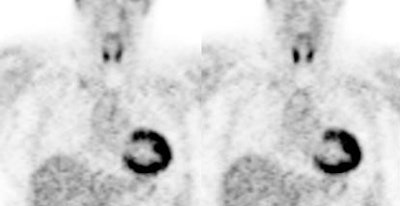

|

Myocardial activity: Myocardial uptake can be very variable. The patient on the left below had a glucose level of 97 prior to FDG injection. Despite the normal serum glucose, note the intense cardiac activity in this patient. The patient on the right was a diabetic patient with a blood glucose of 169- note that there is no myocardial uptake in this patient despite the elevated glucose level. |

|

|